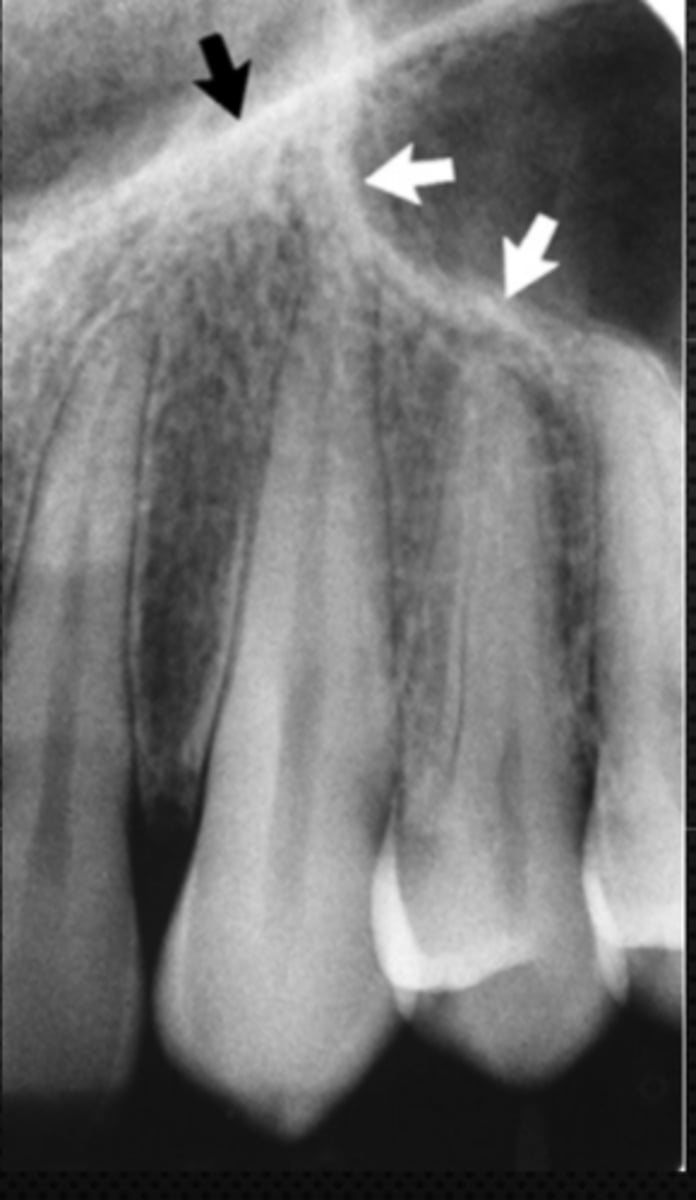

Black arrow - Nasal septum

White arrow- nasal conchae

Identify both structures

New cards

Black arrow - Floor of the nasal cavity

White arrow- maxillary sinus

Identify the structures

<p>Identify the structures</p>